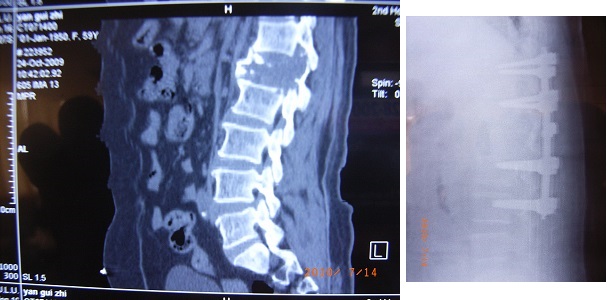

腰1椎体肿瘤,病理骨折,行腰1椎体切除,肋骨植入钉棒系统内固定术,病理为浆细胞瘤,现患者行动自如。